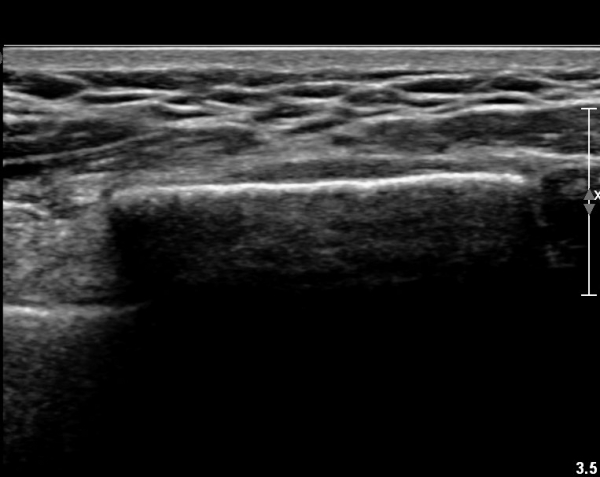

Á¶±Ý ´õ ¸»´ÜÀ¸·Î À̵¿ÇÏ´Ï Äá¾Ë»À ÇÇÁú°ñ ¿¬¼Ó¼º ¼Ò½ÇÀÌ °üÂûµÊ(»çÁö 3),